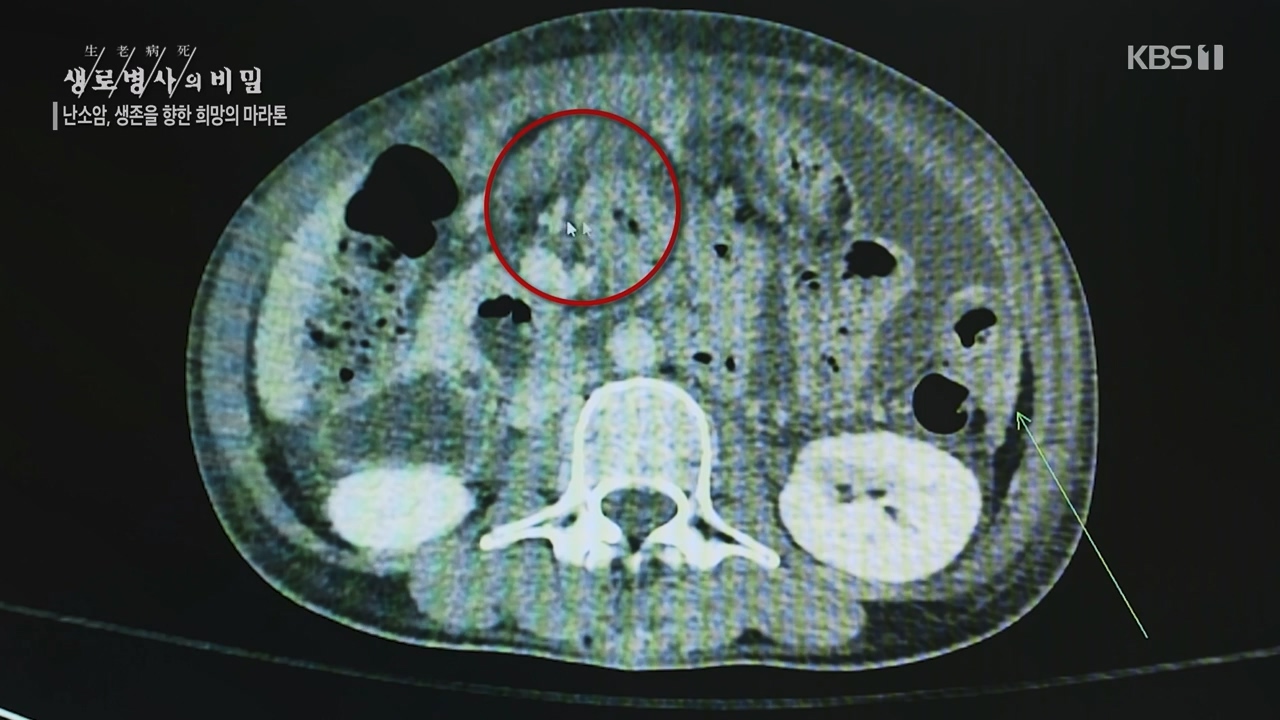

소리 없는 불청객’ 난소암과 싸우는 사람들…KBS1 ‘생로병사의 비밀’ 방송을 보고나서.

* 소리 없는 불청객’ 난소암과 싸우는 사람들…KBS1 ‘생로병사의 비밀’ 방송 재밌게 잘봤습니다.

‘소리 없는 불청객’ 난소암과 싸우는 사람들…KBS1 ‘생로병사의 비밀’

어느 날 갑자기 난소암 판정을 받았다.” 난소암 환자들이 입을 모아 하는 이야기다. 별다른 ...